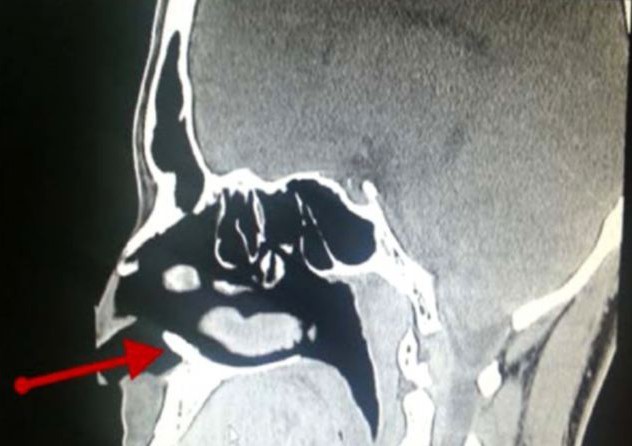

Лекарите са открили зъб в носа на мъж от Саудитска Арабия. Той страдал от постоянно течение на кръв от носа. След хилядите прегледи и изследвания медиците разбрали, че в обонятелния му орган расте не какво и да е, а истински зъб, пише Metro, цитиран от iNews.bg.

22-годишното момче имал проблеми с носа си всеки месец в продължение на 3 години. Накрая лекарите след много прегледи разбрали, че има зъб, който го драска от вътрешната страна на ноздрата и това причинява кървенето.

Лекарите били много изненадани от откритието тъй като момчето имало перфектен набор от зъби в устата си. След проведена операция зъбът, който измъчил момчето е премахнат.